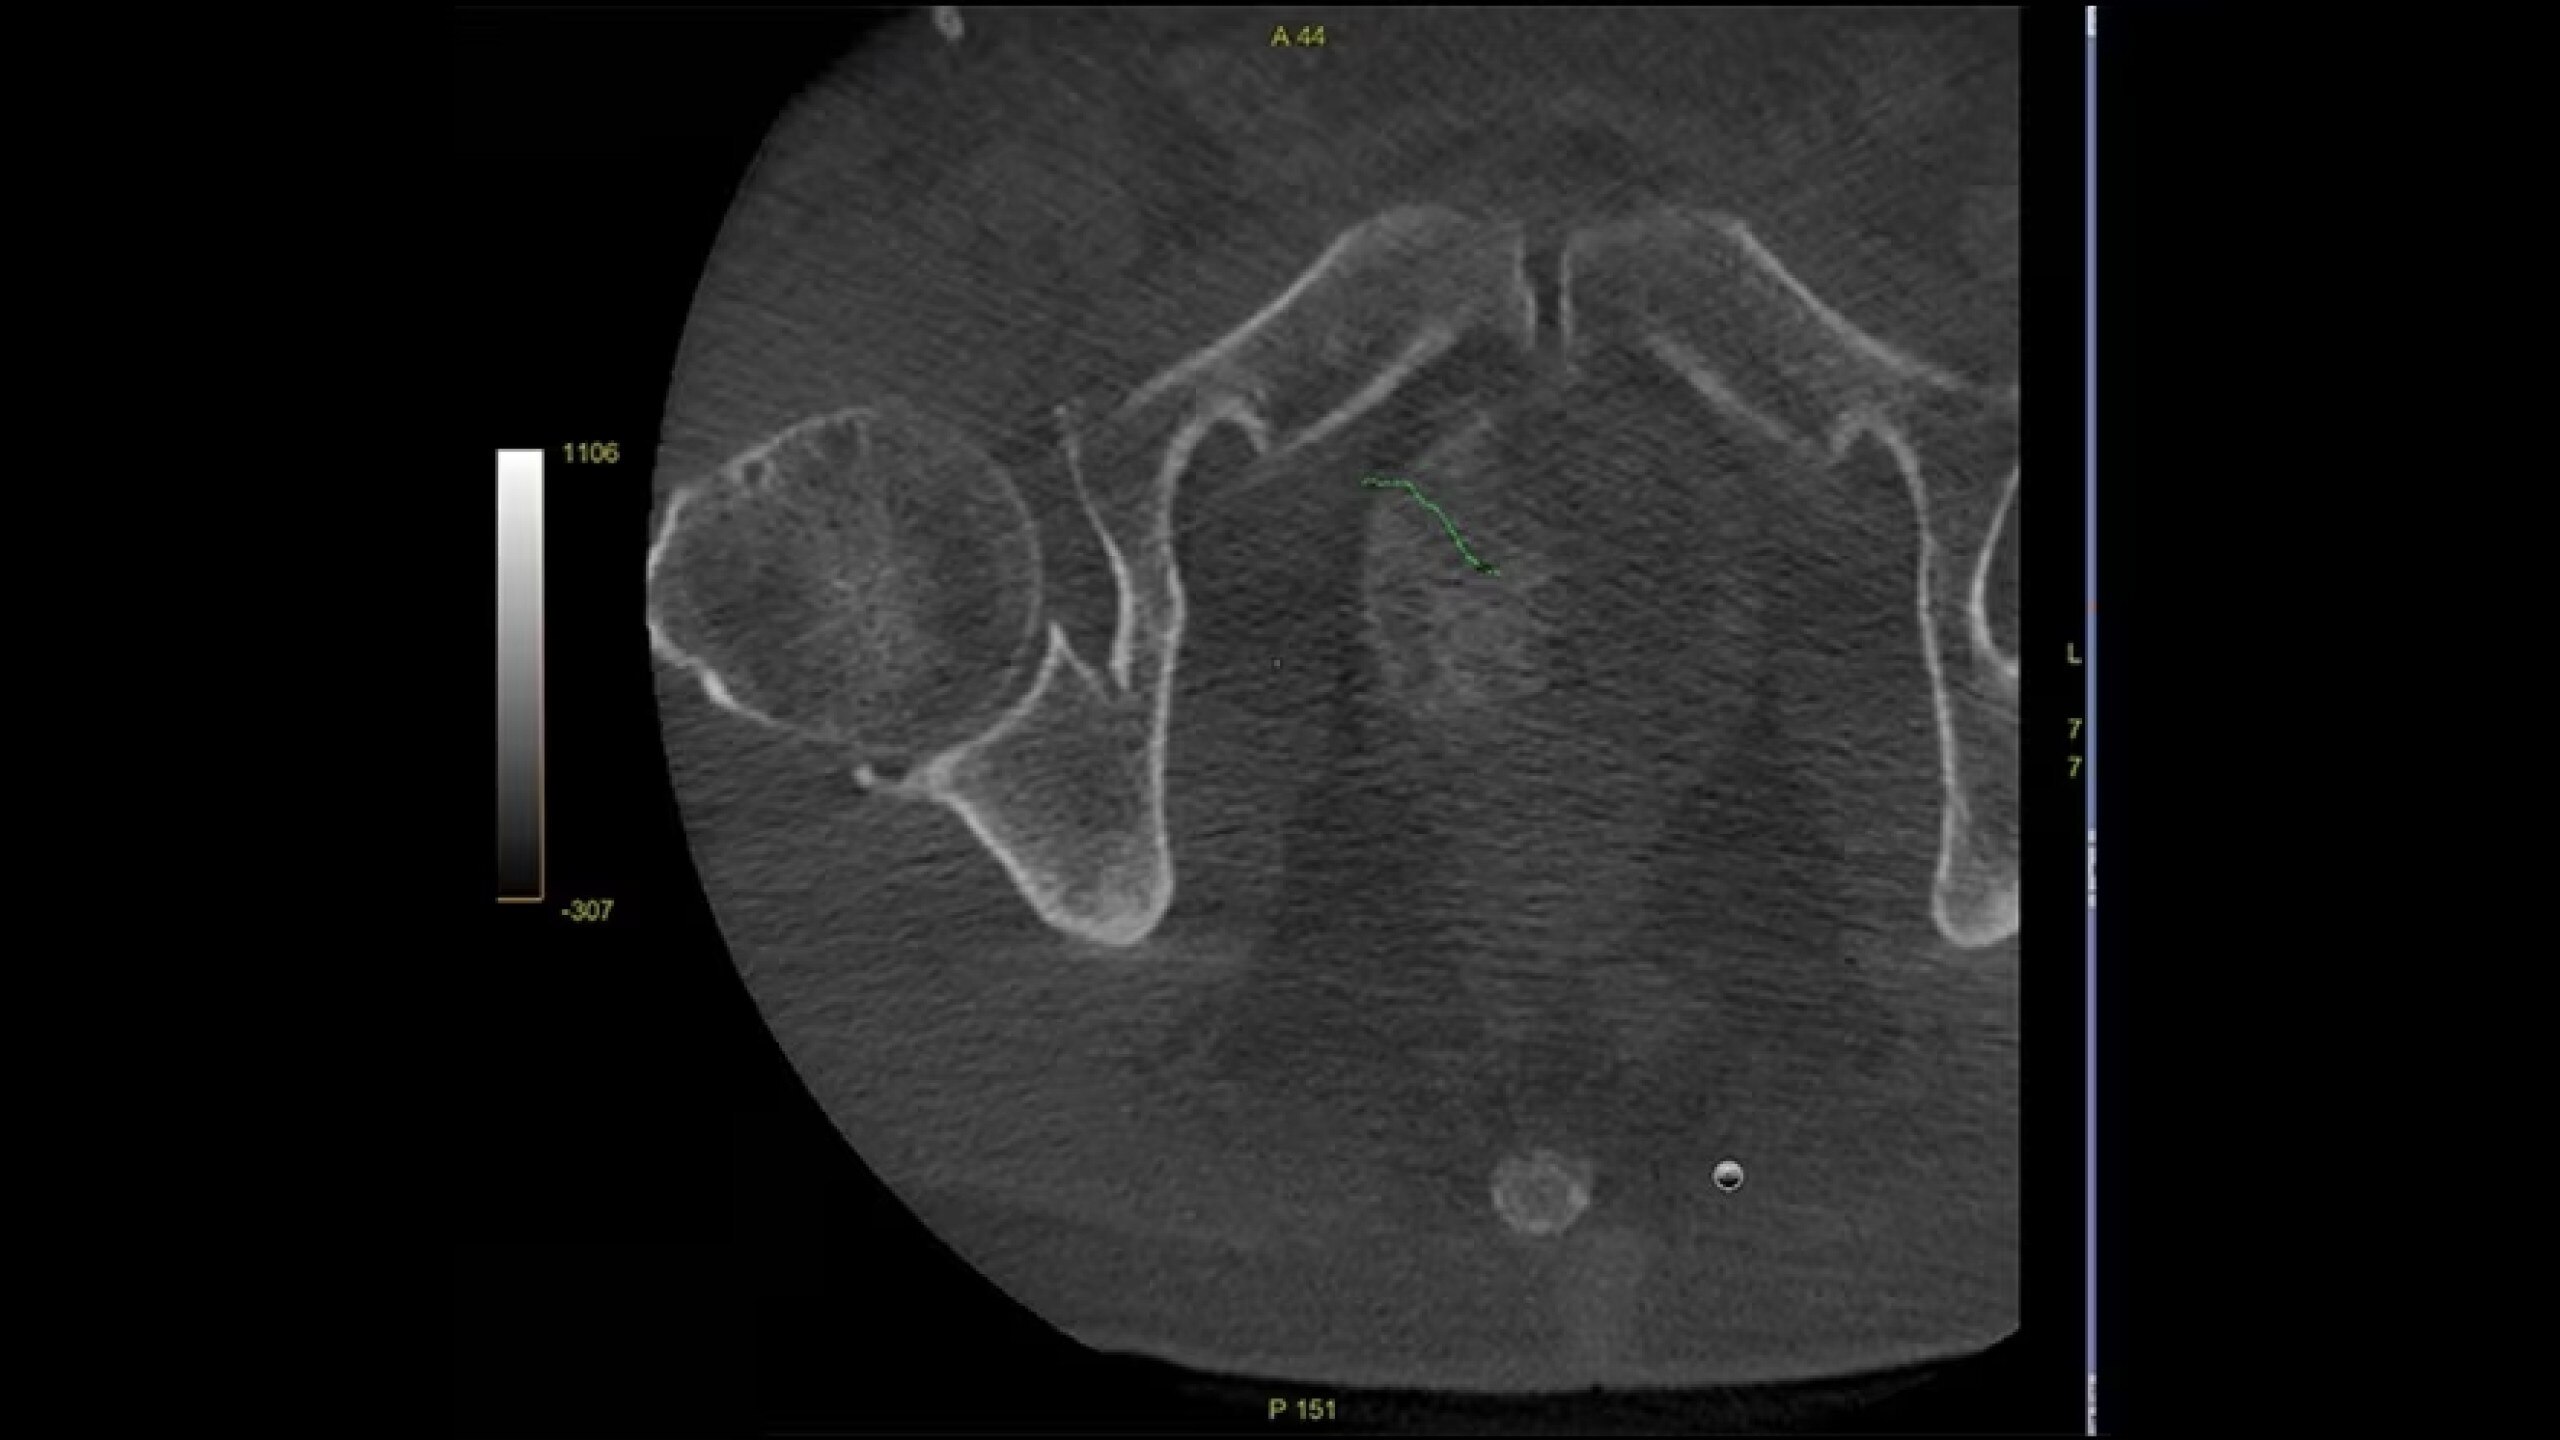

Embo ASSIST is an AI-based augmented guidance solution designed to define optimal embolization strategies and streamline your clinical workflow.

Segment vasculature from CBCT in one click

Visualize multiple vessels and navigate in cross sections to facilitate planning